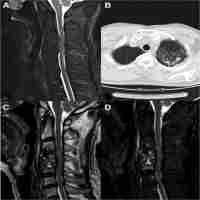

| Abstract | It is well documented that there is significant motion in the unfused segments above and below a fused segment during anterior cervical discectomy and fusion but exact nature of this motion is not well known. The current finite element study showed that likelihood of adjacent segment degeneration is higher in a two level fusion than a one level fusion. Also, the analyses showed that two level fusion at upper cervical levels more likely to degenerate above and below than two level fusion at lower cervical levels. |